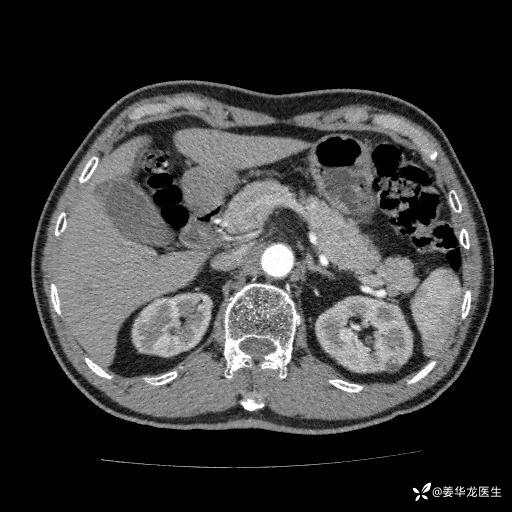

左肾中心型肾门部肿瘤39mm×34mm×36mm,右肾GFR25ml/min,部分切还是全切?

患者75岁老年男性,体重50kg,无高血压、肾病、糖尿病等基础病,检查发现左肾中心型肾门部肿瘤,右肾GFR只有25ml,无肉眼血尿,无镜下血尿。入院验血常规检查均正常,包括肾功能,肌酐102.7umol/L.

二、左肾肿瘤与左肾集合系、左肾动静脉关系密切,左肾部分切除术可行吗?成功率有多大?成功部分切后,肾功能还有多少?